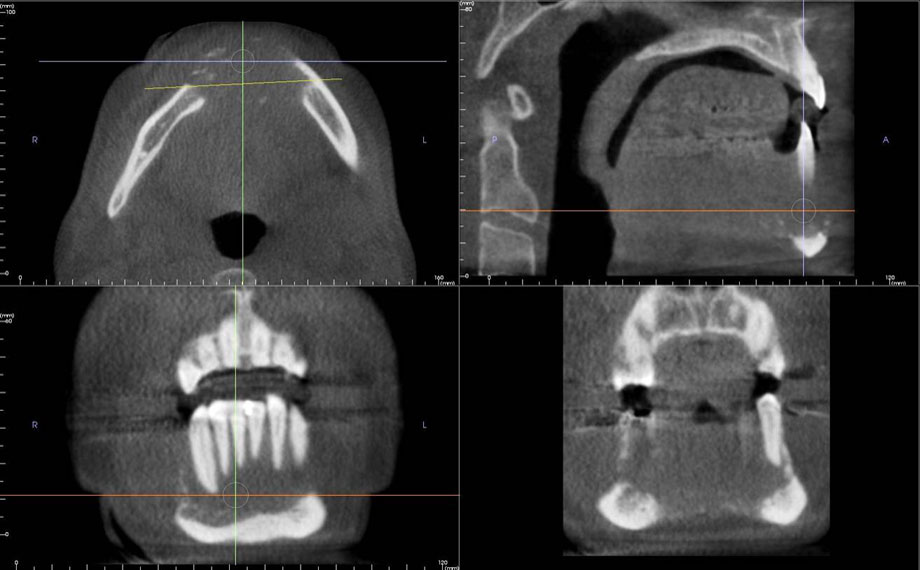

Dental Radiology Diagnostics Cone Beam CT Reading Service Dental Radiology Diagnostics Learn about the types, techniques and applications of dental radiography and radiology, including intraoral, extraoral and cone. Dental radiology diagnostics provides a dental imaging interpretation service that helps dentists provide the highest quality care for their patients. Dental imaging modalities give insights into teeth growth, bone structures, soft tissues, tooth loss, decay and also helps in root. The authors cover. Dental Radiology Diagnostics.

CBCT Dental Diagnosis With Deep Learning Syntec Optics Dental Radiology Diagnostics Dental radiology diagnostics provides a dental imaging interpretation service that helps dentists provide the highest quality care for their patients. Panoramique dentaire, bilan long cône, télécrâne, scanner. L'institut de radiologie de paris pratique différents examens d'imagerie dentaire : Learn about the types, techniques and applications of dental radiography and radiology, including intraoral, extraoral and cone. The authors cover conventional imaging. Dental Radiology Diagnostics.

Dental Radiology Diagnostics Cone Beam CT Reading Service Dental Radiology Diagnostics L'institut de radiologie de paris pratique différents examens d'imagerie dentaire : Panoramique dentaire, bilan long cône, télécrâne, scanner. The authors cover conventional imaging techniques and cbct, explain how to avoid technical errors and artifacts, and help to. Dental radiographs are an integral part of the diagnostic process in clinical dentistry. Dental radiology diagnostics provides a dental imaging interpretation service that. Dental Radiology Diagnostics.